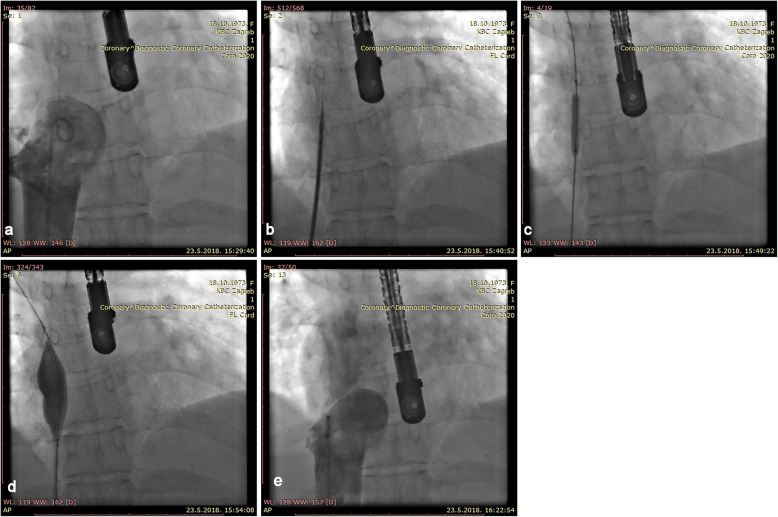

Percutaneous intervention was indicated. The patient was primed with 300 mg of Clopidogrel and 325 mg of Aspirin. Venous access was obtained via 6 French sheaths in the right femoral vein. Unfractionated heparin (5.000 units) was given. Venography was performed via pigtail catheter. It revealed a short, completely occluded segment (thick web) between the right atrium (RA) and IVC. After an unsuccessful attempt to puncture the membrane with a distal tip of an Amplatz stiff wire (J curve, 0,035 Cook Medical, Bloomington, IN, USA), the thick web was punctured with a curved needle through a transseptal introducer sheath (Mullins Sheath 8 Fr and Brokenborough needle 18 gauge, Medtronic, Minneapolis, MN, USA), in the same manner as we would puncture the interatrial septum. After confirming the position of the needle by contrast injection, the sheath was advanced over the needle into the RA, beyond the occlusion. Then a 0.032 J-tip wire was negotiated across the web and was parked in the right subclavian vein. The membrane was first dilated with an available 6,0/20 mm non compliant coronary balloon (NC Emerge, Boston Scientific, Boston MA, USA), with 16 atm, followed by dilatation with a bigger non-complined peripheral balloon16/20 mm with 20 atm (Atlas Gold, Bard Vascular, Tempe AZ USA), with poor result. Sequentially, several balloon dilatations with 30/40 mm semi-compliant balloon (Z-med II, Numed-Braun, Bethlehem, PA, USA), with 4 atm pressure was performed, resulting in immediate recoil. Satisfactory result was achieved after the inflated big balloon was sharply withdrawn through the membrane (a “Rashkind-like” manoeuvre). Stenting was not possible, due to the membrane position (Fig. 3).

Fig. 3.

INTERVENTION a Angiography shows a complete obstruction of the blood flow between IVC and RA, b puncture with a Brockenbrough needle, c dilatation of the membrane with a 6/20 mm NC balloon. d dilatation with a 16/20 mm balloon. e final angiography of IVS, after withdrawn of a 30/40 balloon through the membrane, showing restoration of IVC to RA flow patency